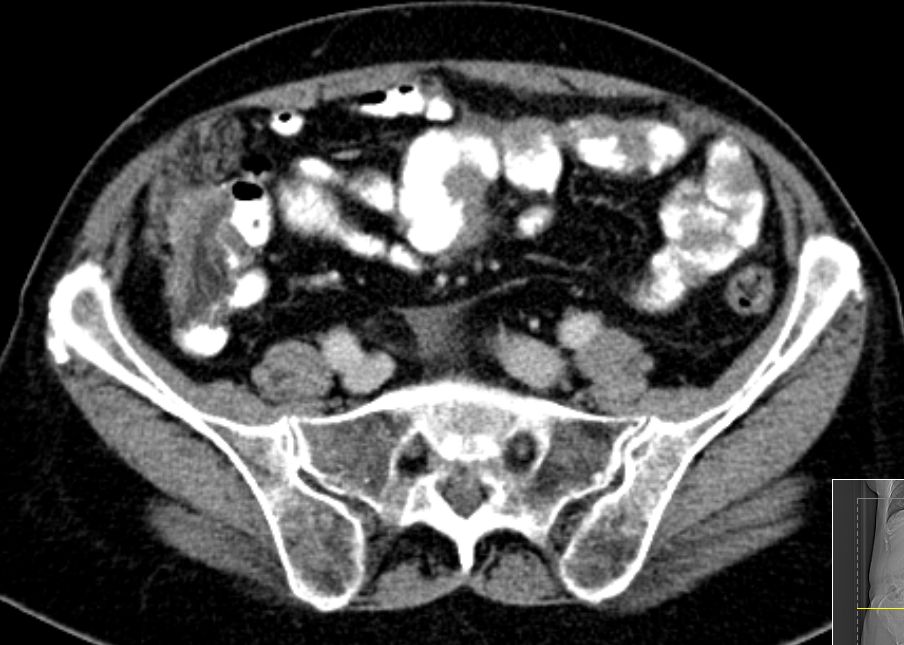

72-jährige Frau mit Peritonealkarziose nach HE mit

Adnexen vor 16 Jahren.

Histologie: Low-grade-serös-papilläres Karzinom

Intraoperatv ausgedehnte Karzinose der Darmserosa und des

Mesenteriums.